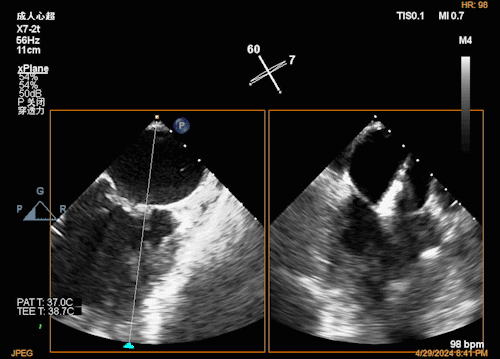

团队在反流最严重的2区精准植入1枚二尖瓣夹,即刻反流下降至微量,血压即刻上升20mmHg,跨瓣压差不升反降,由3mmHg降至2mmHg,改善效果明显,手术仅耗时一个半小时。 这是时隔四年继2020年指导开展区域内首例TAVR(经导管主动脉瓣置换)手术之后,陈茂教授再次带领华西团队,指导开展内自同城区域首例TEER术。陈茂教授对四院心内科心超图像的采集、房间隔穿刺的技巧、手术流程细节的把握、团队的默契配合、术前术后的管理表示称赞,鼓励四院心内科再接再厉造福区域患者。 患者为71岁老年女性,反复出现心累、气促已经超过10年,10多年来心衰的症状逐渐加重,间隔时间越来越短,且近1个月来已经3次因心衰住院,本次住院前已经无法耐受缓慢步行、如厕等日常生活,BNP超过了3000ng/ml。心电图为房颤,心超示左心室明显增大(65mm),重度二尖瓣反流(4+,CarpentierI+IIIb型),射血分数仅为31%。前叶长度:2.27cm且瓣尖增厚,后叶长度:1.14cm且局部钙化,瓣口面积:4.08cm2,反流宽度:1.7cm。患者及家属均拒绝外科开胸手术。 难点: 1.食道超声下该患者房间隔较厚较韧,且粗测高度仅为4.0cm,对穿刺的位置和技巧有较高要求; 2.左心扩大,反流宽度约17mm,放一个夹子可能不能有效解决反流,如放两个夹子需side by side 平行放置,但放置两个夹子有术后狭窄的风险; 3.前后叶对合似有间隙,若选用长宽夹子,会增加瓣叶张力,有瓣叶撕裂的风险,若选用短宽夹子,其捕获瓣叶的难度将增加; 4.患者心功能极差,手术需稳、准、快,不能耐受任何并发症风险。 影像资料 房间隔穿刺